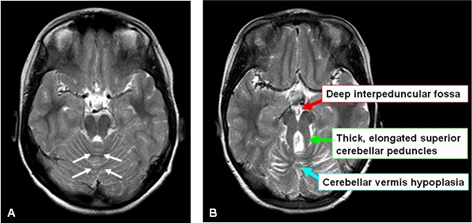

The pathognomonic neuro-radiological sign on the brain MRI, the “molar tooth sign,” indicates the cerebellar vermis hypoplasia and brainstem abnormalities (deep interpeduncular fossa, and thick and elongated superior cerebellar peduncles) (Figure 2). The fourth ventricle can have an appearance of 'bat wing'.